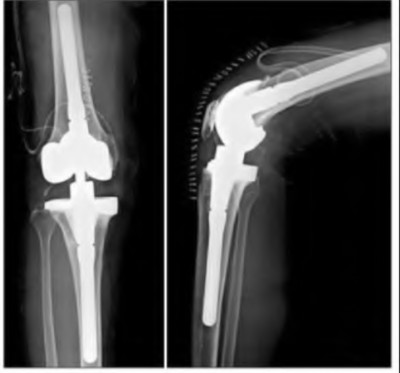

A 64-year-old woman with osteoarthritis underwent bilateral total knee replacement 3 years ago. Current radiographs are shown in Figure A. She reports a 3-month history of bilateral knee pain while at rest and increasing swelling in the knees. Her ESR and CRP are elevated and bilateral knee aspiration cultures reveal Staphylococcus aureus. What is the most likely outcome if the patient undergoes simultaneous, bilateral knee resection arthroplasty with cement spacer and a course of intravenous antibiotics?

1) Prosthesis reimplantation with need for multiple surgical debridements at 2-year follow-up

2) 20% risk of above knee amputation

3) Retention of antibiotic cement spacer and low chance of successful prosthesis reimplantation at 2-year follow-up

4) 50% rate of conversion to knee fusion following resection arthroplasty

5) Successful prosthesis reimplantation at 2-year follow-up with less than 20% revision rate

This patient presents with bilateral total knee arthroplasty infection.

Wolff et al report Level 4 evidence of 18 patients followed an average of 5 years after bilateral TKA infection. Eleven patients were initially treated with attempts to salvage the original prosthesis (polyethylene l liner exchange, I&D, IV antibiotics and chronic oral suppressive antibiotics. With prosthesis retention, 9/11 (81%) developed recurrent infection at a mean of 15 months. The other 10 patients initially underwent resection arthroplasty with cement spacer and a course of IV antibiotics. Seven of the 10 (70%) underwent reimplantation at a mean of 3 months (6 weeks to 5 months) and none of the patients required revision at mean of two years follow up. Satisfaction rates were significantly higher among this group of patients. The authors advocate the protocol of bilateral TKA resection arthroplasty with cement antibiotic spacer and course of IV antibiotics followed by prosthesis reimplantation.